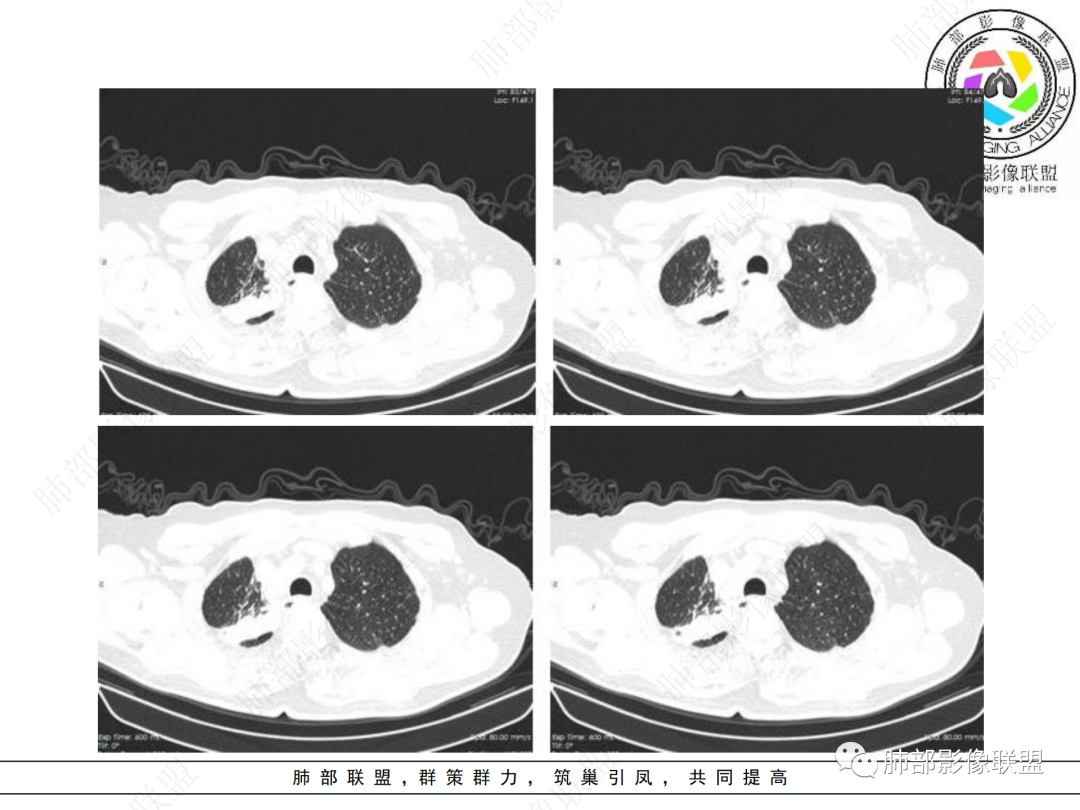

右肺上叶可见一团块影,边界清,有膨隆有凹陷,边缘可见毛刺,斜裂可见牵拉,不均匀强化,内可见液化,临近支气管未见明确阻塞,考虑腺癌可能,鉴别脓肿,结核等

右肺上叶团块,边缘毛糙,长索条,周围斑点影,邻近胸膜增厚,不均匀强化,其内小低密度灶边界清,考虑炎性肉芽肿,腺癌待排

老年男性,慢性病程,右肺上叶团块影,边界清晰,边缘毛刺,脐凹征,胸膜牵拉,不均匀强化,支气管壁增厚,考虑恶性,腺癌可能,鉴别肉芽肿、结核

老年男性,右肺上叶体积小,见高密度团块,边缘模糊,并见多发长索条,增强后不均匀强化,考虑炎性肉芽肿性病变,鉴别腺癌

病程长,右肺上叶团片影,边缘毛糙,部分膨隆,长索条,周围长条索及结节,邻近胸膜增厚,不均匀强化,首先考虑炎性肉芽肿,鉴别腺癌

右肺上叶见不规则团块,边缘清晰,周围可见长索条及斑片影,胸膜顶增厚,右侧斜裂部分增厚,右上肺体积略缩小,增强后不均匀强化,考虑炎性肉芽肿性病变,结核?鉴别腺癌

右肺上叶体积变小,见不规则实性病灶,边缘有平直,长软毛刺,邻近胸膜明显增厚,叶间胸膜牵拉上提、局部凹陷;病灶周围不干净,可见长索条影;近端支气管壁略增厚。增强后增强不均匀,有低密度坏死,间隔较厚。考虑慢性炎性肉芽肿,结核可能,鉴别腺癌。